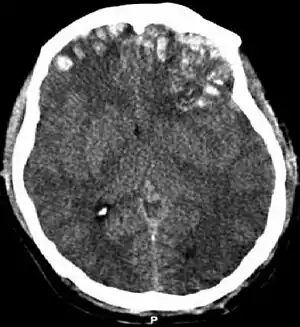

| CT scan showing cerebral contusions, hemorrhage within the hemispheres, subdural hematoma on the left, and skull fractures[1] | |